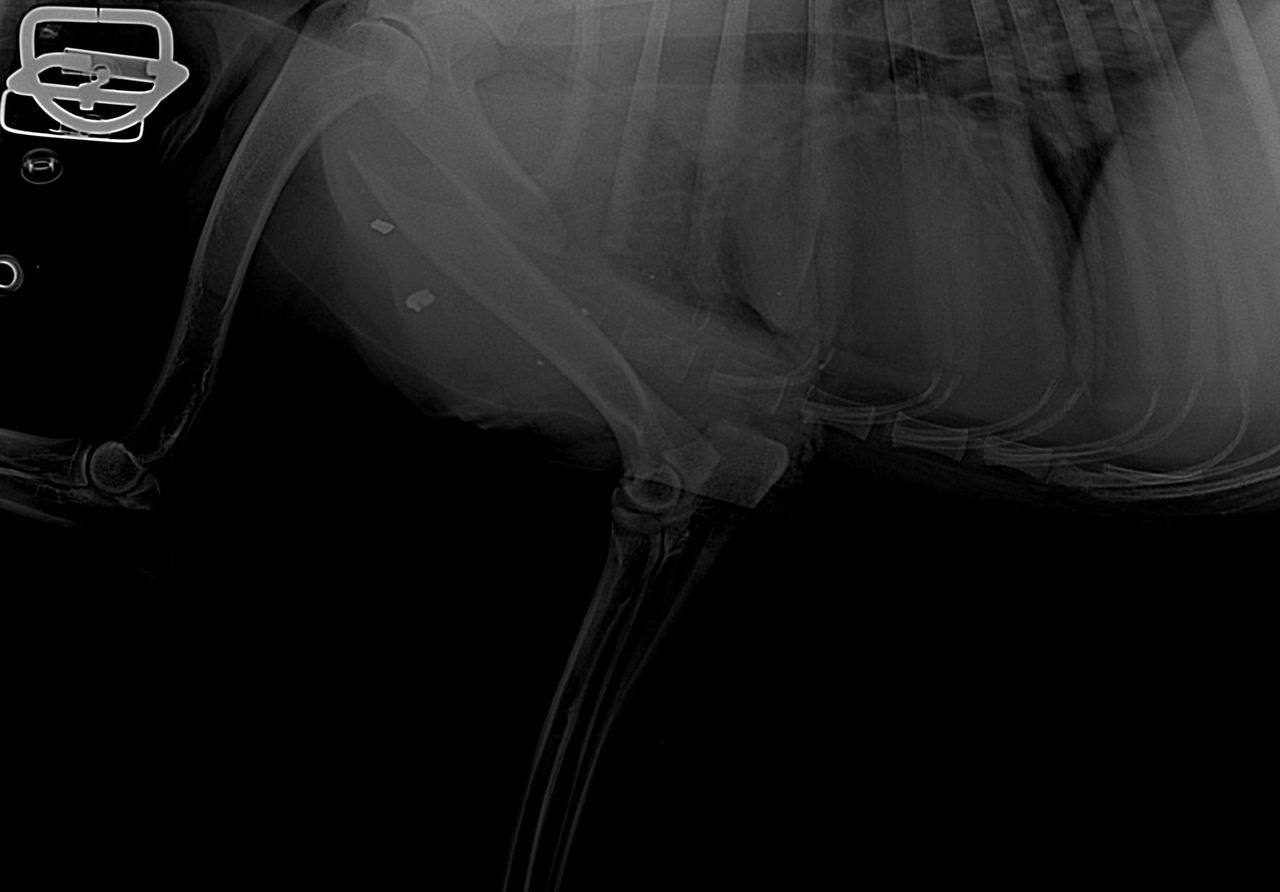

В приюте живут 300 собак, одна из них серьёзно пострадала – у пса перелом со смещением. Осколки посекли здания и окна.